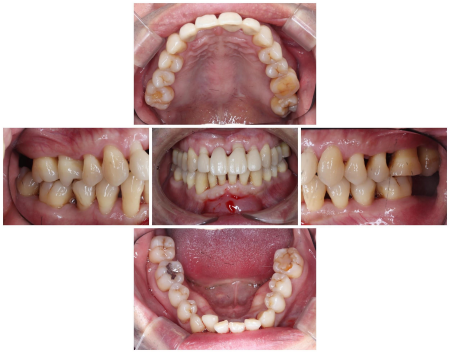

治療前

拝見したところ、上の前歯数本に出血と揺れが生じていました。

特に右上の前歯(中切歯/1番)は揺れが著しく、他院で応急処置がされており、口腔内で使用できる接着剤「スーパーボンド」で固定された状態でのご来院でした。

歯ぐきの検査やレントゲン撮影を行った結果、若くして歯を支える組織に炎症が起こる「若年性歯周病」が全体的に進行した状態と診断しました。

歯の表面や歯ぐきの内側には、歯周病の原因となる細菌の塊「プラーク」や、プラークが硬く石灰化した「歯石」の付着が認められました。